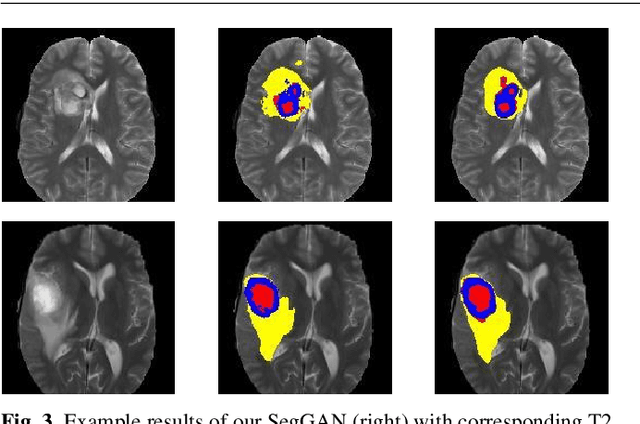

Abstract:Inspired by classic generative adversarial networks (GAN), we propose a novel end-to-end adversarial neural network, called SegAN, for the task of medical image segmentation. Since image segmentation requires dense, pixel-level labeling, the single scalar real/fake output of a classic GAN's discriminator may be ineffective in producing stable and sufficient gradient feedback to the networks. Instead, we use a fully convolutional neural network as the segmentor to generate segmentation label maps, and propose a novel adversarial critic network with a multi-scale $L_1$ loss function to force the critic and segmentor to learn both global and local features that capture long- and short-range spatial relationships between pixels. In our SegAN framework, the segmentor and critic networks are trained in an alternating fashion in a min-max game: The critic takes as input a pair of images, (original_image $*$ predicted_label_map, original_image $*$ ground_truth_label_map), and then is trained by maximizing a multi-scale loss function; The segmentor is trained with only gradients passed along by the critic, with the aim to minimize the multi-scale loss function. We show that such a SegAN framework is more effective and stable for the segmentation task, and it leads to better performance than the state-of-the-art U-net segmentation method. We tested our SegAN method using datasets from the MICCAI BRATS brain tumor segmentation challenge. Extensive experimental results demonstrate the effectiveness of the proposed SegAN with multi-scale loss: on BRATS 2013 SegAN gives performance comparable to the state-of-the-art for whole tumor and tumor core segmentation while achieves better precision and sensitivity for Gd-enhance tumor core segmentation; on BRATS 2015 SegAN achieves better performance than the state-of-the-art in both dice score and precision.